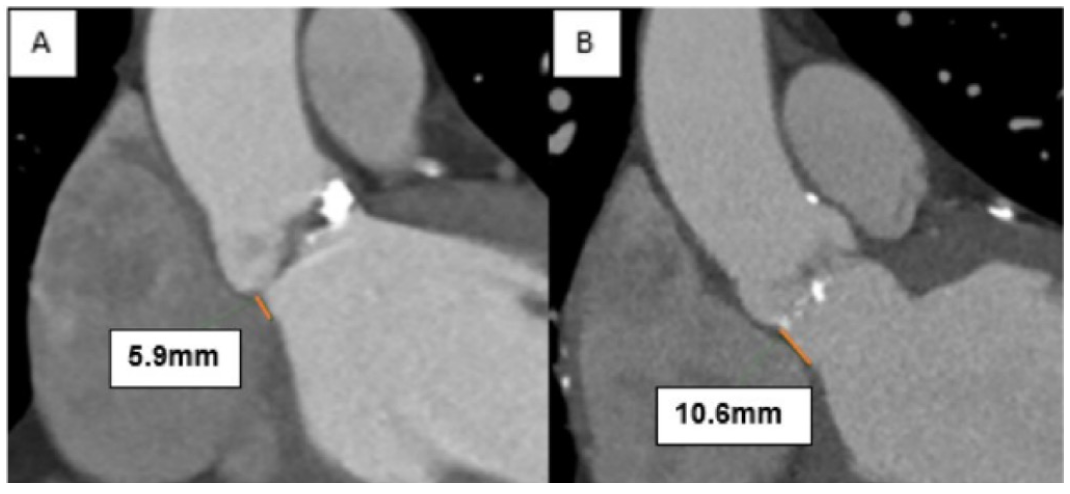

Protocol for computed tomography (CT) analysis. Measurements of aortic annular diameter, area, and perimeter were performed before each procedure by the operating structural interventional cardiologist. Aortic valvular and LVOT degrees of calcification were graded semiquantitatively. MSL was measured in a dedicated coronal view, and defined as the perpendicular distance from the annular plane to the beginning of the muscular septum (Figure 5).